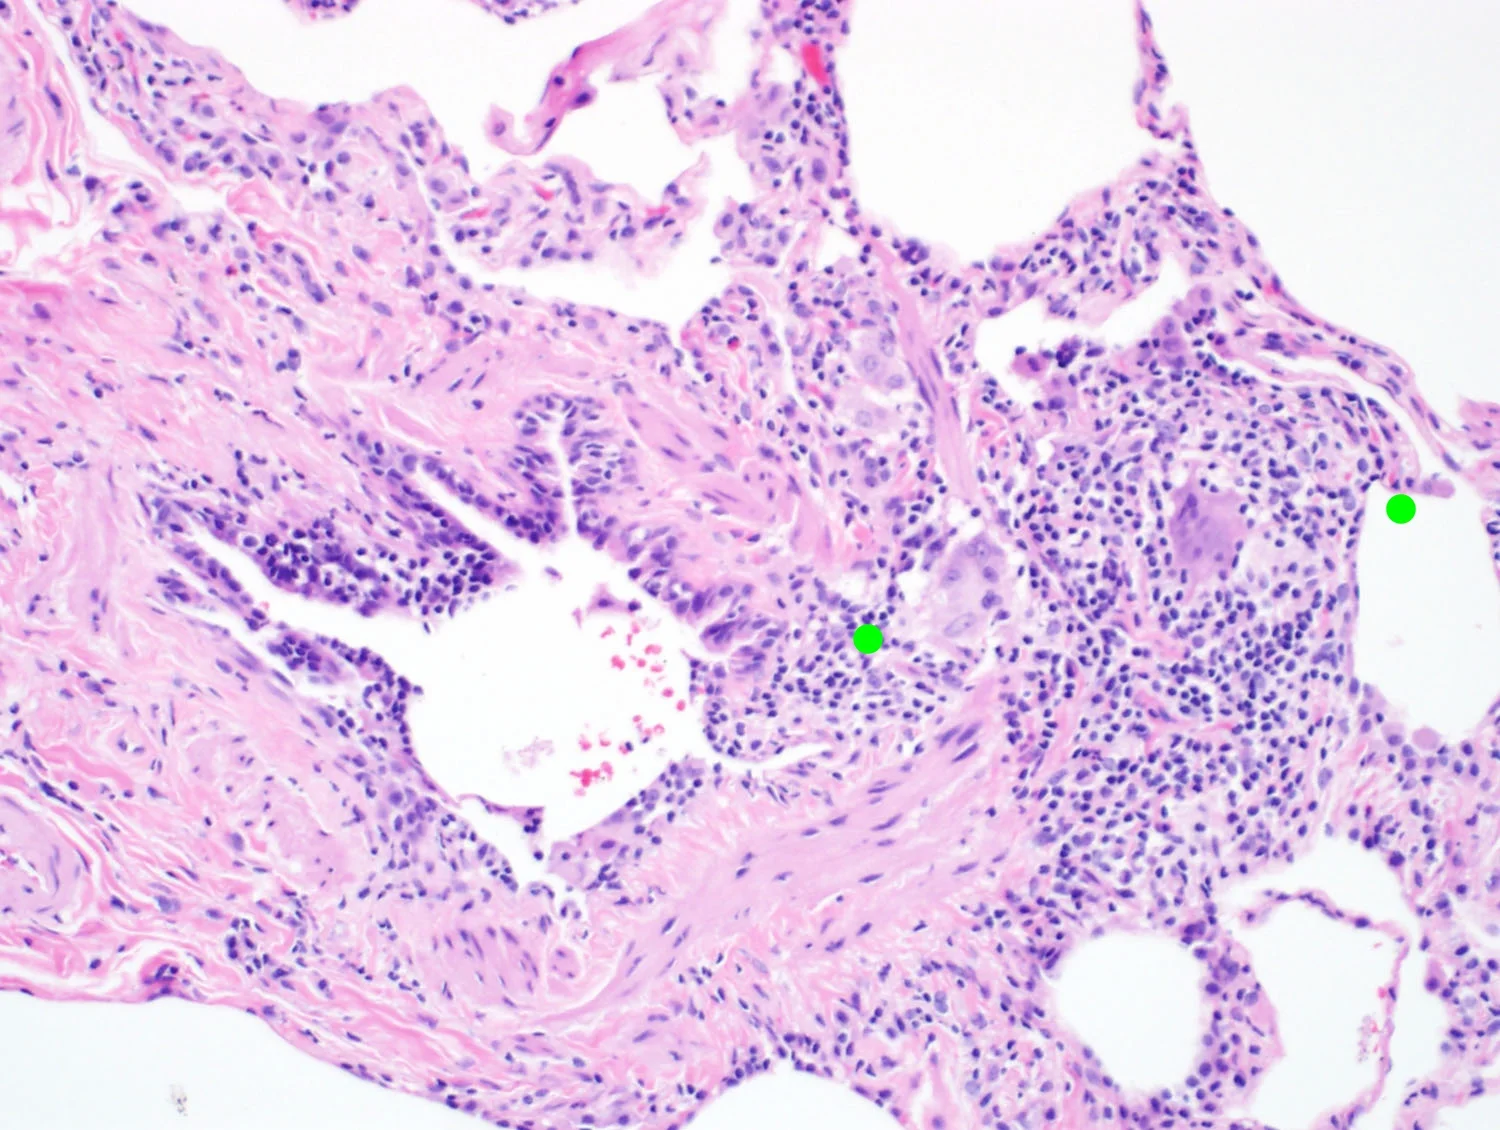

Significant fibrosis accentuated around airways.

Pulmonary fibrosis with UIP, NSIP, or airway centered fibrosis

Variable amounts of peribronchiolar metaplasia

Peribronchiolar metaplasia

Bridging fibrosis (airway to airway)

Airway centered fibrosis

CrHP with airway centered fibrosis